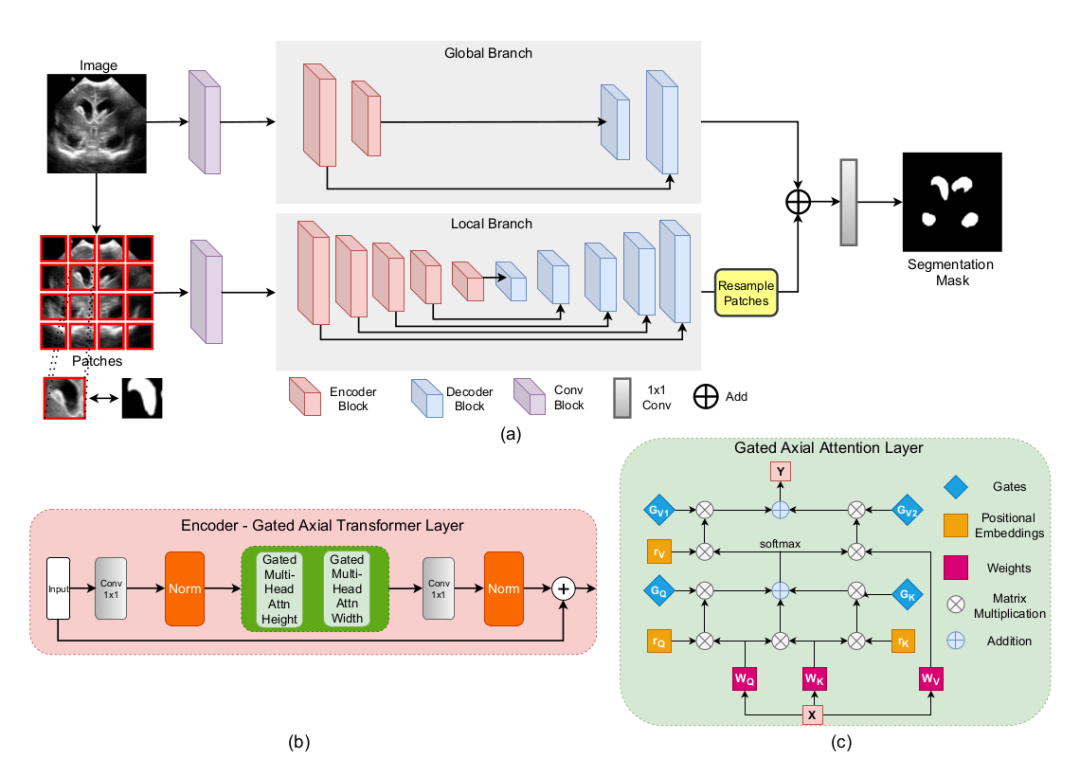

《Medical Transformer: Gated Axial-Attention for Medical Image Segmentation》